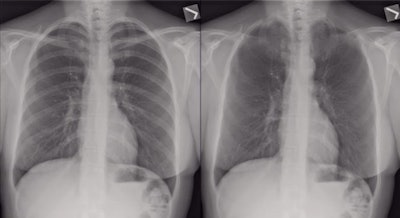

The technique is bone suppression imaging, in which a postprocessing bone suppression algorithm can be used to suppress the conspicuity of bones on chest radiographs to create corresponding bone suppression chest images.

The average nodule size was 28 ± 10 mm (range, 9-49 mm). The 95 nodules were all solid nodules, and 91 were obscured by the clavicle or ribs. The mean value of the area under the receiver operator characteristics (ROC) curve for the four observers significantly improved from 0.844 with the standard images alone to 0.887 with the bone suppression images (p < 0.001).

The mean sensitivity for the four observers also significantly improved, from 73% with standard radiographs alone to 78% with the additional bone suppression images. Specificity increased with the bone suppression images from 83% to 84.5%.